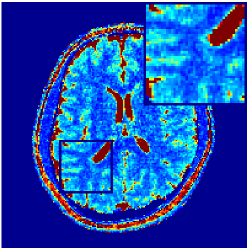

Two sets of experiments were conducted here: first, we used the 2D and 3D acquisition sequences for scanning a healthy volunteer’s brain (real-world acquisitions). Figures 6 and 7 display the parametric maps reconstructed from 2D spiral and radial readouts. We computed the T1, T2 and proton density (PD) maps using baseline reconstruction algorithms ZF, VS, LR, FLOR, AIR-MRF and our proposed LRTV. While baselines use DM either for quantitative inference or also during reconstruction (i.e. AIR-MRF), we further compare the DM-free LRTV’s performance when cascaded to DM, KM and MRFResnet for quantitative inference. For the 3D spiral acquisitions we compared LRTV and its closest competitor VS in Figure 8. Outcomes from other tested algorithm are displayed in the supplementary materials (Figure S5). Since FLOR does not use dimensionality-reduction, our system ran out of memory during 3D reconstruction; hence results are not reported in this case.

VI-E1 Discussion

The LRTV-DM and LRTV-MRFResnet perform on par, and both outperform all tested baselines for reconstructing T1, T2 and PD maps in all acquisition schemes. This can be observed both visually in Figures 6, 7, 8, S2 and S3, and quantitatively in Table IV across all tested metrics. Other baselines were unable to successfully remove the under-sampling artefacts in TSMIs, and these errors propagated to the parameter inference phase and resulted in inaccurate maps. Temporal-only priors incorporated within LR are shown insufficient to regularise the inverse problem and LR sometimes (e.g. 2D spiral acquisitions) can admit solutions with even stronger artefacts than the model-free ZF baseline. This issue was previously studied for other non-Cartesian MRF readouts that similar to our spiral/radial trajectories, miss to sample the corners of the k-space in all timeframes (see section 2.2.2 and figure 2 in [19]). In the absence of reference for the k-space corners information, the LR iterations despite minimising the objective can converge to solutions with high-frequency artefacts, as visible in the computed maps. This highlights the need for adding an appropriate spatial-domain regularisation. FLOR reduces the LR’s artefacts but this improvement is limited because the suggested nuclear norm penalty does not incorporate an explicit spatial regularisation. Further for reducing artefacts, FLOR can introduce an undesirable bias in the computed T1/T2 maps e.g. see error maps in Figures S2 and S3. The non model-based VS baseline incorporates spatial regularisation and results in spatially smoother maps than ZF and LR, but it is unable to output artefact-free images. Further and consistent with our in-vitro experiment, we observe that VS overestimates the T2 values (e.g. in White and Grey matter regions) in tested 2D acquisitions i.e. the spatial regularisation trades off agains the quantification accuracy. The model-based AIR-MRF adds spatial regularisation through 2D/3D low-pass Gaussian filters however this trades off the sharpness of the computed maps and can increase the errors at the tissue boundaries (we searched Gaussian spreads that keep the blurs and high-frequency artefacts minimal). For our acquisition readouts, Gaussian filters performed better than disk filters of [19] for avoiding strong Gibbs artefacts. On the other hand, the spatiotemporally regularised LRTV greatly improves the TSMI reconstructions i.e. 4 dB enhancement compared to the closest competitor baseline (Table IV). This enables computing accurate and aliased-free multi-parametric inference using DM or the DM-free learning-based alternative MRFResnet as visible in Figures 6, 7, 8, S2 and S3. MRResnet and DM score competitive quantitative inference results i.e. T1 and T2 MAPE less than 5% and 9%, respectively (Table IV). KM also outputs comparably accurate T1 maps, however this shallow learning model despite having a model size larger than MRFResnet, is unable to learn accurate T2/PD quantification and it results in poor estimated maps, consistent with our observations in section VI-C.